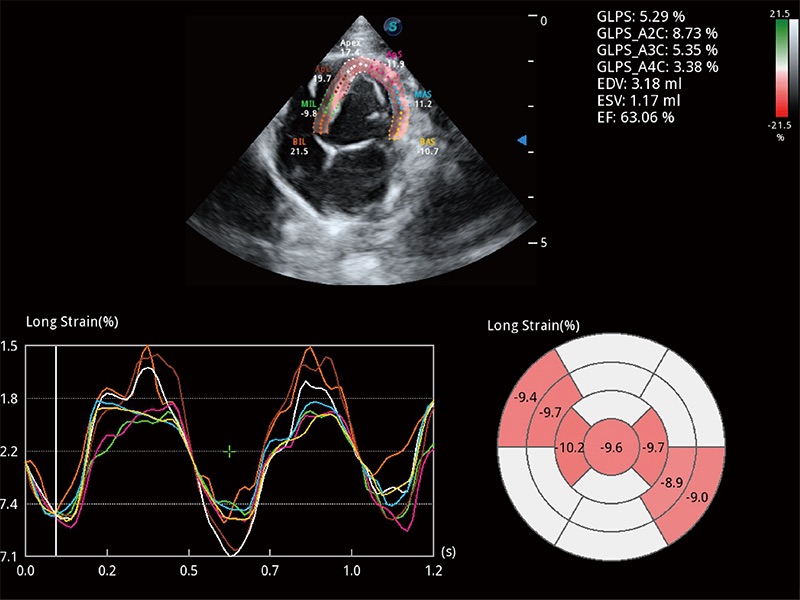

通過心肌識(shí)別技術(shù)與二維斑點(diǎn)追蹤技術(shù)相結(jié)合,對(duì)心臟的超聲圖像進(jìn)行量化分析。計(jì)算心肌17個(gè)節(jié)段的應(yīng)變、應(yīng)變率、速度、位移等,并通過牛眼圖的形式進(jìn)行呈現(xiàn)。